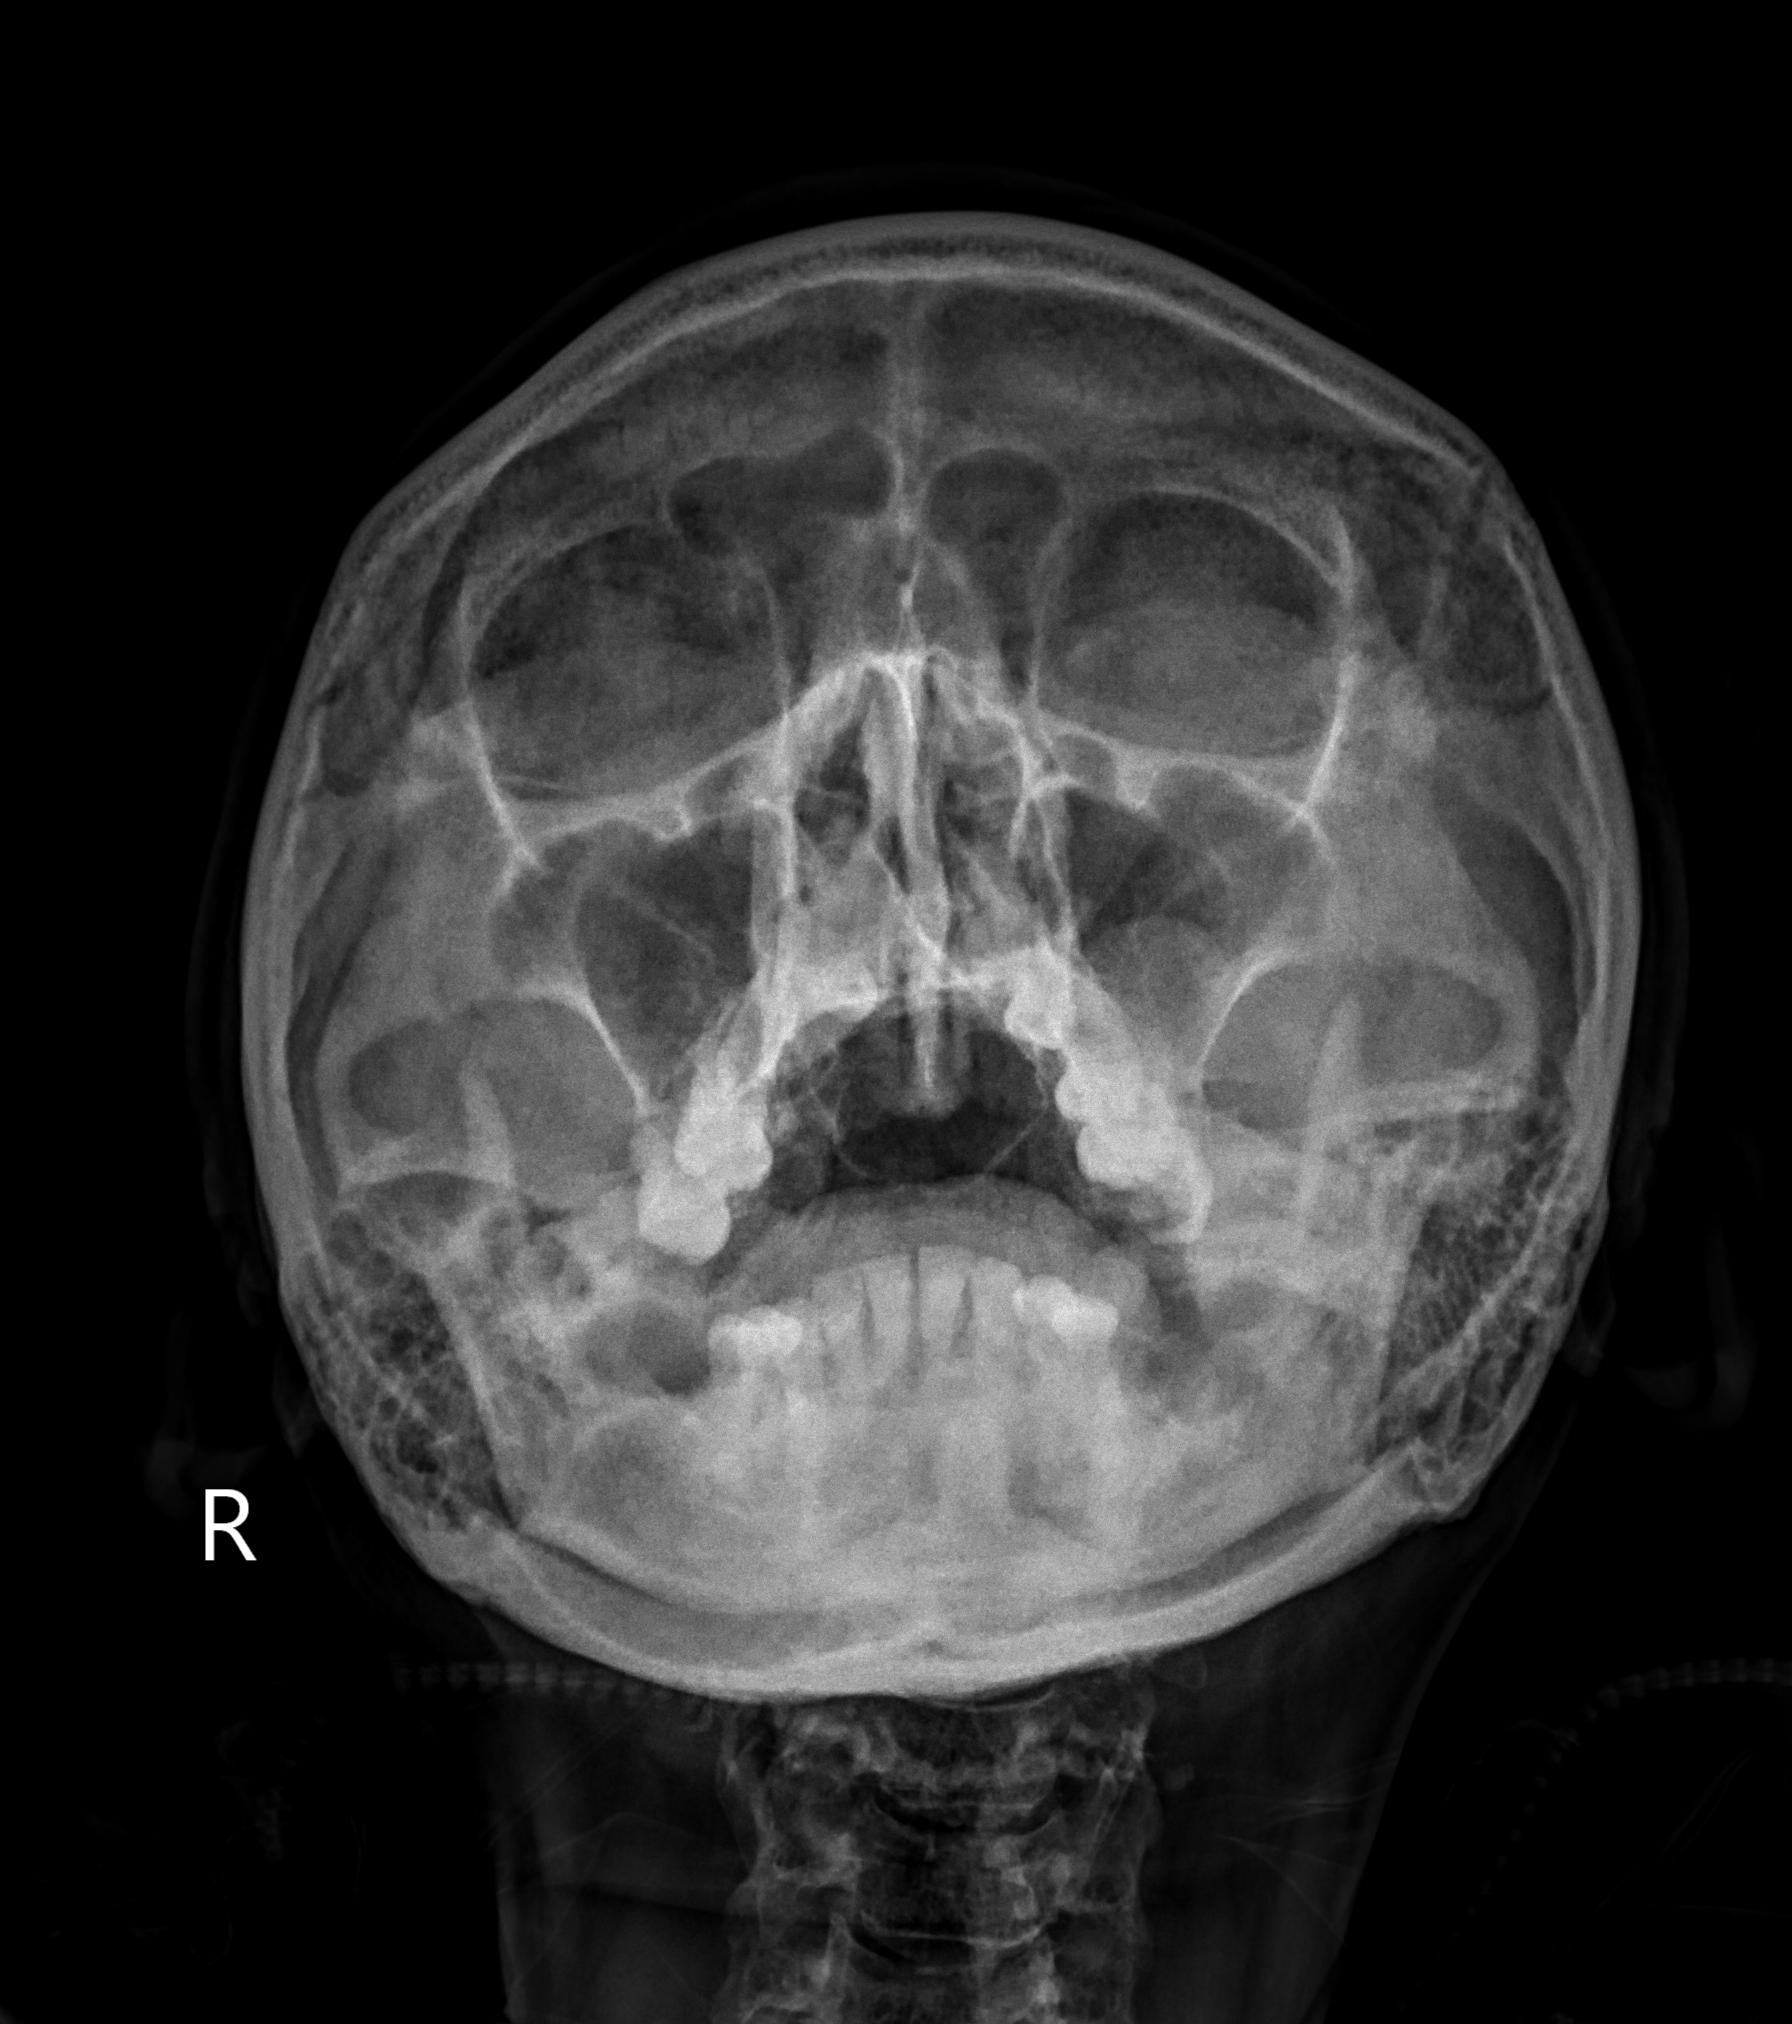

X-quang đầu mặt cổ

X-quang xoang - polyp xoang hàm